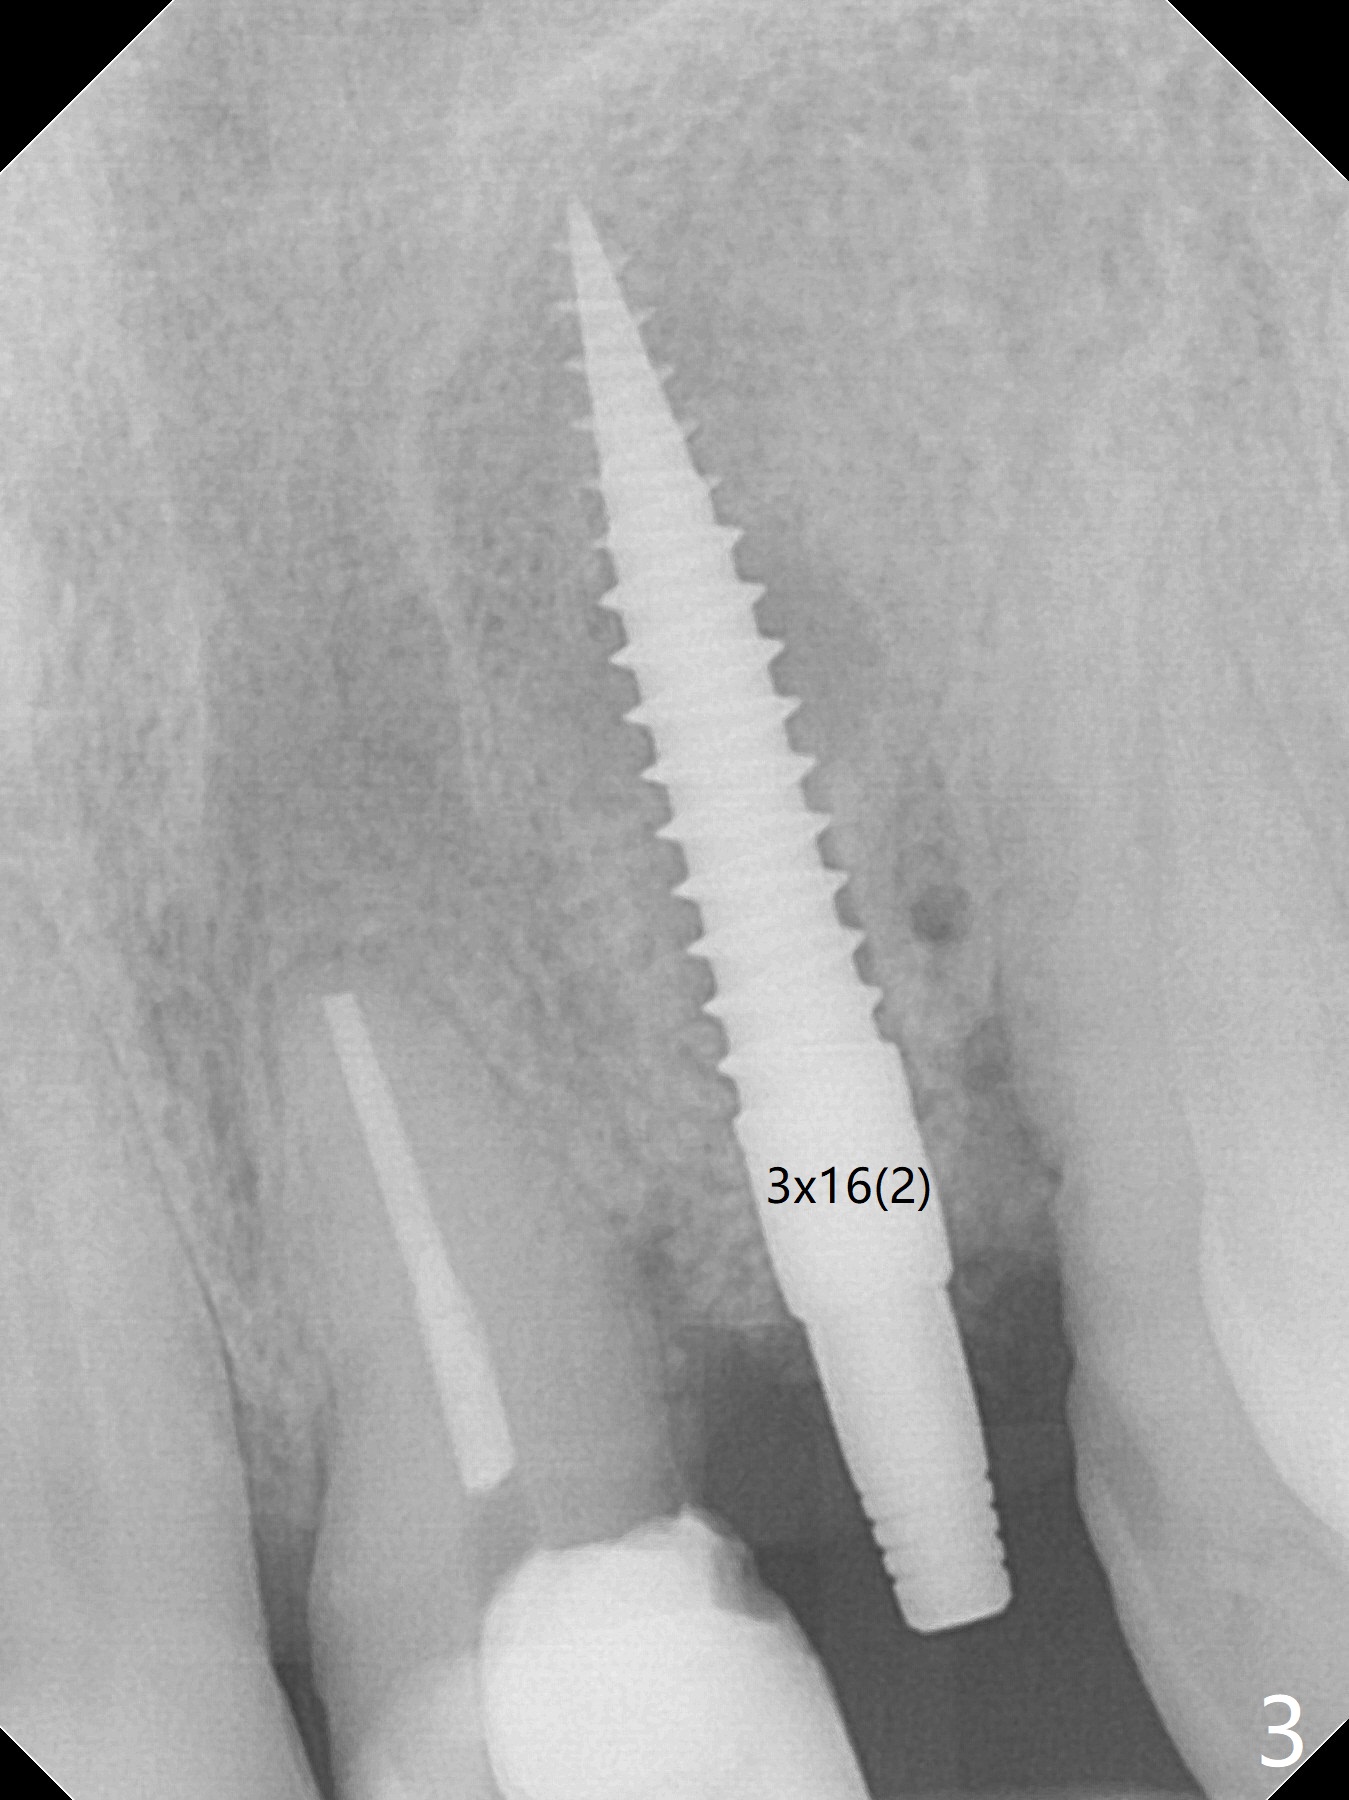

When the 67-year-old man returns for #23-26 crown/FPD cementation, the tooth #10 has fractured with necrotic pulp (Fig.1) and periapical radiolucency (Fig.2 (CT coronal section) *). He requests immediate implant since he has difficulty in getting ride from out of state. After curettage of the apical granulation tissue, a 3x16(2) mm 1-piece implant is placed with 20 Ncm because of slight overprep using 2 mm drill (Fig.3). Postop CT shows that the implant does not seem to be small (Fig.4). The fracture of the tooth #10 is related to edge-to-edge occlusion with the tooth #22 while the lower restoration is being fabricated in lab (Fig.5). It is easy to achieve occlusal clearance when the immediate provisional is fabricated with normal overjet. The density of the bone immediately next to the implant increases 6 months postop (Fig.6 *). The soft tissue also looks normal.